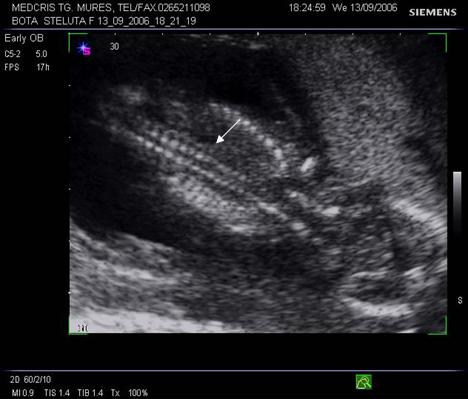

Fig. nr. 22. Coloana vertebrala la fatul de 11 sapt.